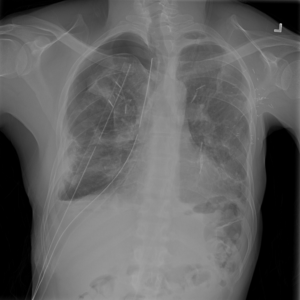

Anomaly detection is the problem of recognizing abnormal inputs based on the seen examples of normal data. Despite recent advances of deep learning in recognizing image anomalies, these methods still prove incapable of handling complex medical images, such as barely visible abnormalities in chest X-rays and metastases in lymph nodes. To address this problem, we introduce a new powerful method of image anomaly detection. It relies on the classical autoencoder approach with a re-designed training pipeline to handle high-resolution, complex images and a robust way of computing an image abnormality score. We revisit the very problem statement of fully unsupervised anomaly detection, where no abnormal examples at all are provided during the model setup. We propose to relax this unrealistic assumption by using a very small number of anomalies of confined variability merely to initiate the search of hyperparameters of the model. We evaluate our solution on natural image datasets with a known benchmark, as well as on two medical datasets containing radiology and digital pathology images. The proposed approach suggests a new strong baseline for image anomaly detection and outperforms state-of-the-art approaches in complex medical image analysis tasks.

翻译:异常检测是根据正常数据实例识别异常输入的问题。尽管在识别图像异常方面最近取得了深层次学习的进展,但这些方法仍然证明无法处理复杂的医学图像,如胸部X光几乎看不到异常和淋巴节点转移等。为了解决这一问题,我们引入了一种新的强有力的图像异常检测方法。它依靠古典的自动解剖器方法,经过重新设计的培训管道来处理高分辨率、复杂图像和图像异常分数。我们重新审视了完全不受监督的异常点检测的非常问题说明,在模型设置期间,根本没有提供异常的例子。我们提议放松这一不现实的假设,仅使用少量有限的异常点来开始搜索模型的超参数。我们评估我们使用已知基准的天然图像数据集以及包含放射学和数字病理图像的两个医疗数据集的解决方案。拟议方法为在复杂的医学图像分析任务中,为图像异常点检测和超常规状态方法提供了新的强基线。